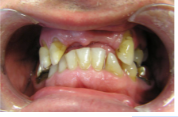

1) 1. Initial situation of teeth anterior and lateral view